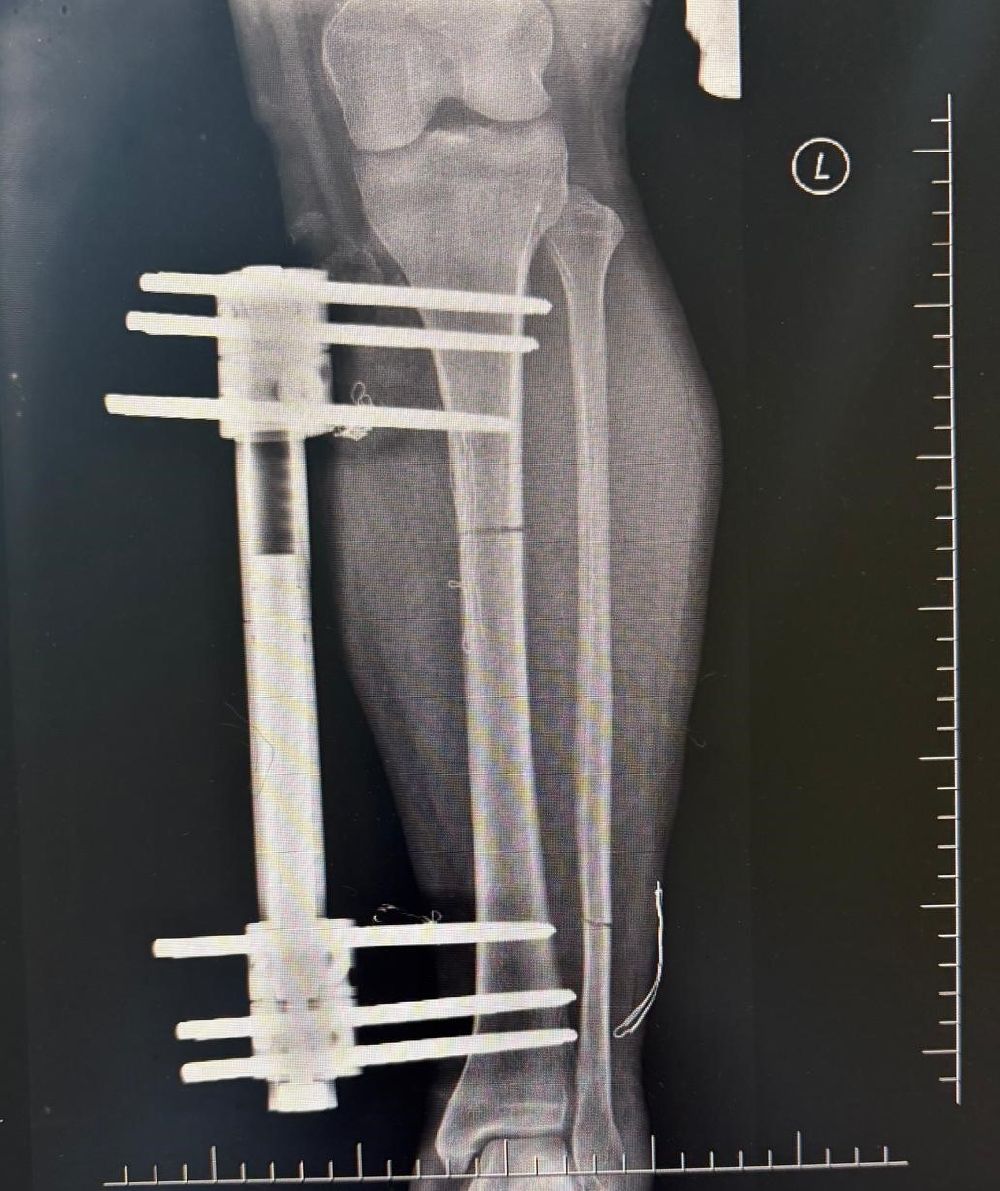

Denizli'de yaşayan 39 yaşındaki M.G., boyunun 1.58 olmasından kaynaklı fiziksel ve bedensel sorunların yaşadığını, daha uzun bir görünüme kavuşmak ve yaşam kalitesini artırmak amacıyla Denizli Özel Tekden Hastanesi'ne başvurdu. Hasta uzun yıllardır boyunun kısalığının gerek günlük yaşamda gerekse sosyal çevresinde çeşitli zorluklara yol açtığını dile getirdi. Aynı zamanda duruş bozukluğu ve bazı fiziksel rahatsızlıklar nedeniyle uzman bir hekime danışma kararı alan M.G., hastanenin Ortopedi ve Travmatoloji bölümünde görev yapan iki uzman doktora başvurdu. Ortopedi ve Travmatoloji Uzmanı Prof. Dr. Mahmut Argün ve Op. Dr. Necip Özateş tarafından detaylı şekilde muayene edildi. Doktorlar tarafından yapılan değerlendirmeler sonucu, hastanın ortalama 10 santimetre daha uzamasının mümkün olduğu belirtildi.

Ameliyat aşamasının ardından gerçekleşen süreci tek tek dile getiren Ortopedi ve Travmatoloji Uzmanı Prof. Dr. Mahmut Argün, "Hastamız 1.58 boyunda olması nedeniyle sürekli boyunun kısalığından dolayı hem fiziksel hem de bedensel rahatsızlıkların olduğunu dile getirdi. Israrla boyunun uzatılmasını bizden talep eden hasta 2 aşamalı olunması gereken muayeneyi 1 aşamalı olmasını istedi. Sol tarafından başlayarak hem femur hem de tibia 5 ila 6 santimetre arasında uzatmayı planladık. Hastamızı ameliyata alıp bu işlemleri gerçekleştirdik. Hasta şuanda uzatma işlemlerinin yapılabilmesi için malzeme yerleştirme aşamasını gerçekleştirdik. Ameliyattan 10 gün sonra uzatma işlemlerini başlayacağız. Uzatma işlemleri yaklaşık 60 gün sürecek. Uzatma işlem süreci geçtikten sonra işlemi durdurup kaynaması için 2-3 ay bekleyeceğiz. Ardından ise hastanın üzerinden malzemeleri yaklaşık 150-200 gün arasında çıkaracağız. Bu tarz işlemler meşakkatli ve özen isteyen ameliyatlar" diye konuştu.

Uzama sürecinde her gün 1 milimetre olmak üzere kurulan mekanizmanın başladığını dile getiren Ortopedi ve Travmatoloji Uzmanı Op. Dr. Necip Özateş, "Her gün 1 milimetre olmak üzere, üzerindeki mekanizma üzerinden hem uyruk kemiği hem kaval kemiği uzatılmaya başlıyor. Hem bu şekilde kemik uzaması hem de bu esnada kemik kaynaması aynı anda olduğu için daha kontrollü bir işlem oluyor. Hedef uzunluğa ulaştığımızda uzatma işlemini sonlandırıyoruz. Sonrasında da kemiğin kaynaması sürecine geçiyoruz" dedi.